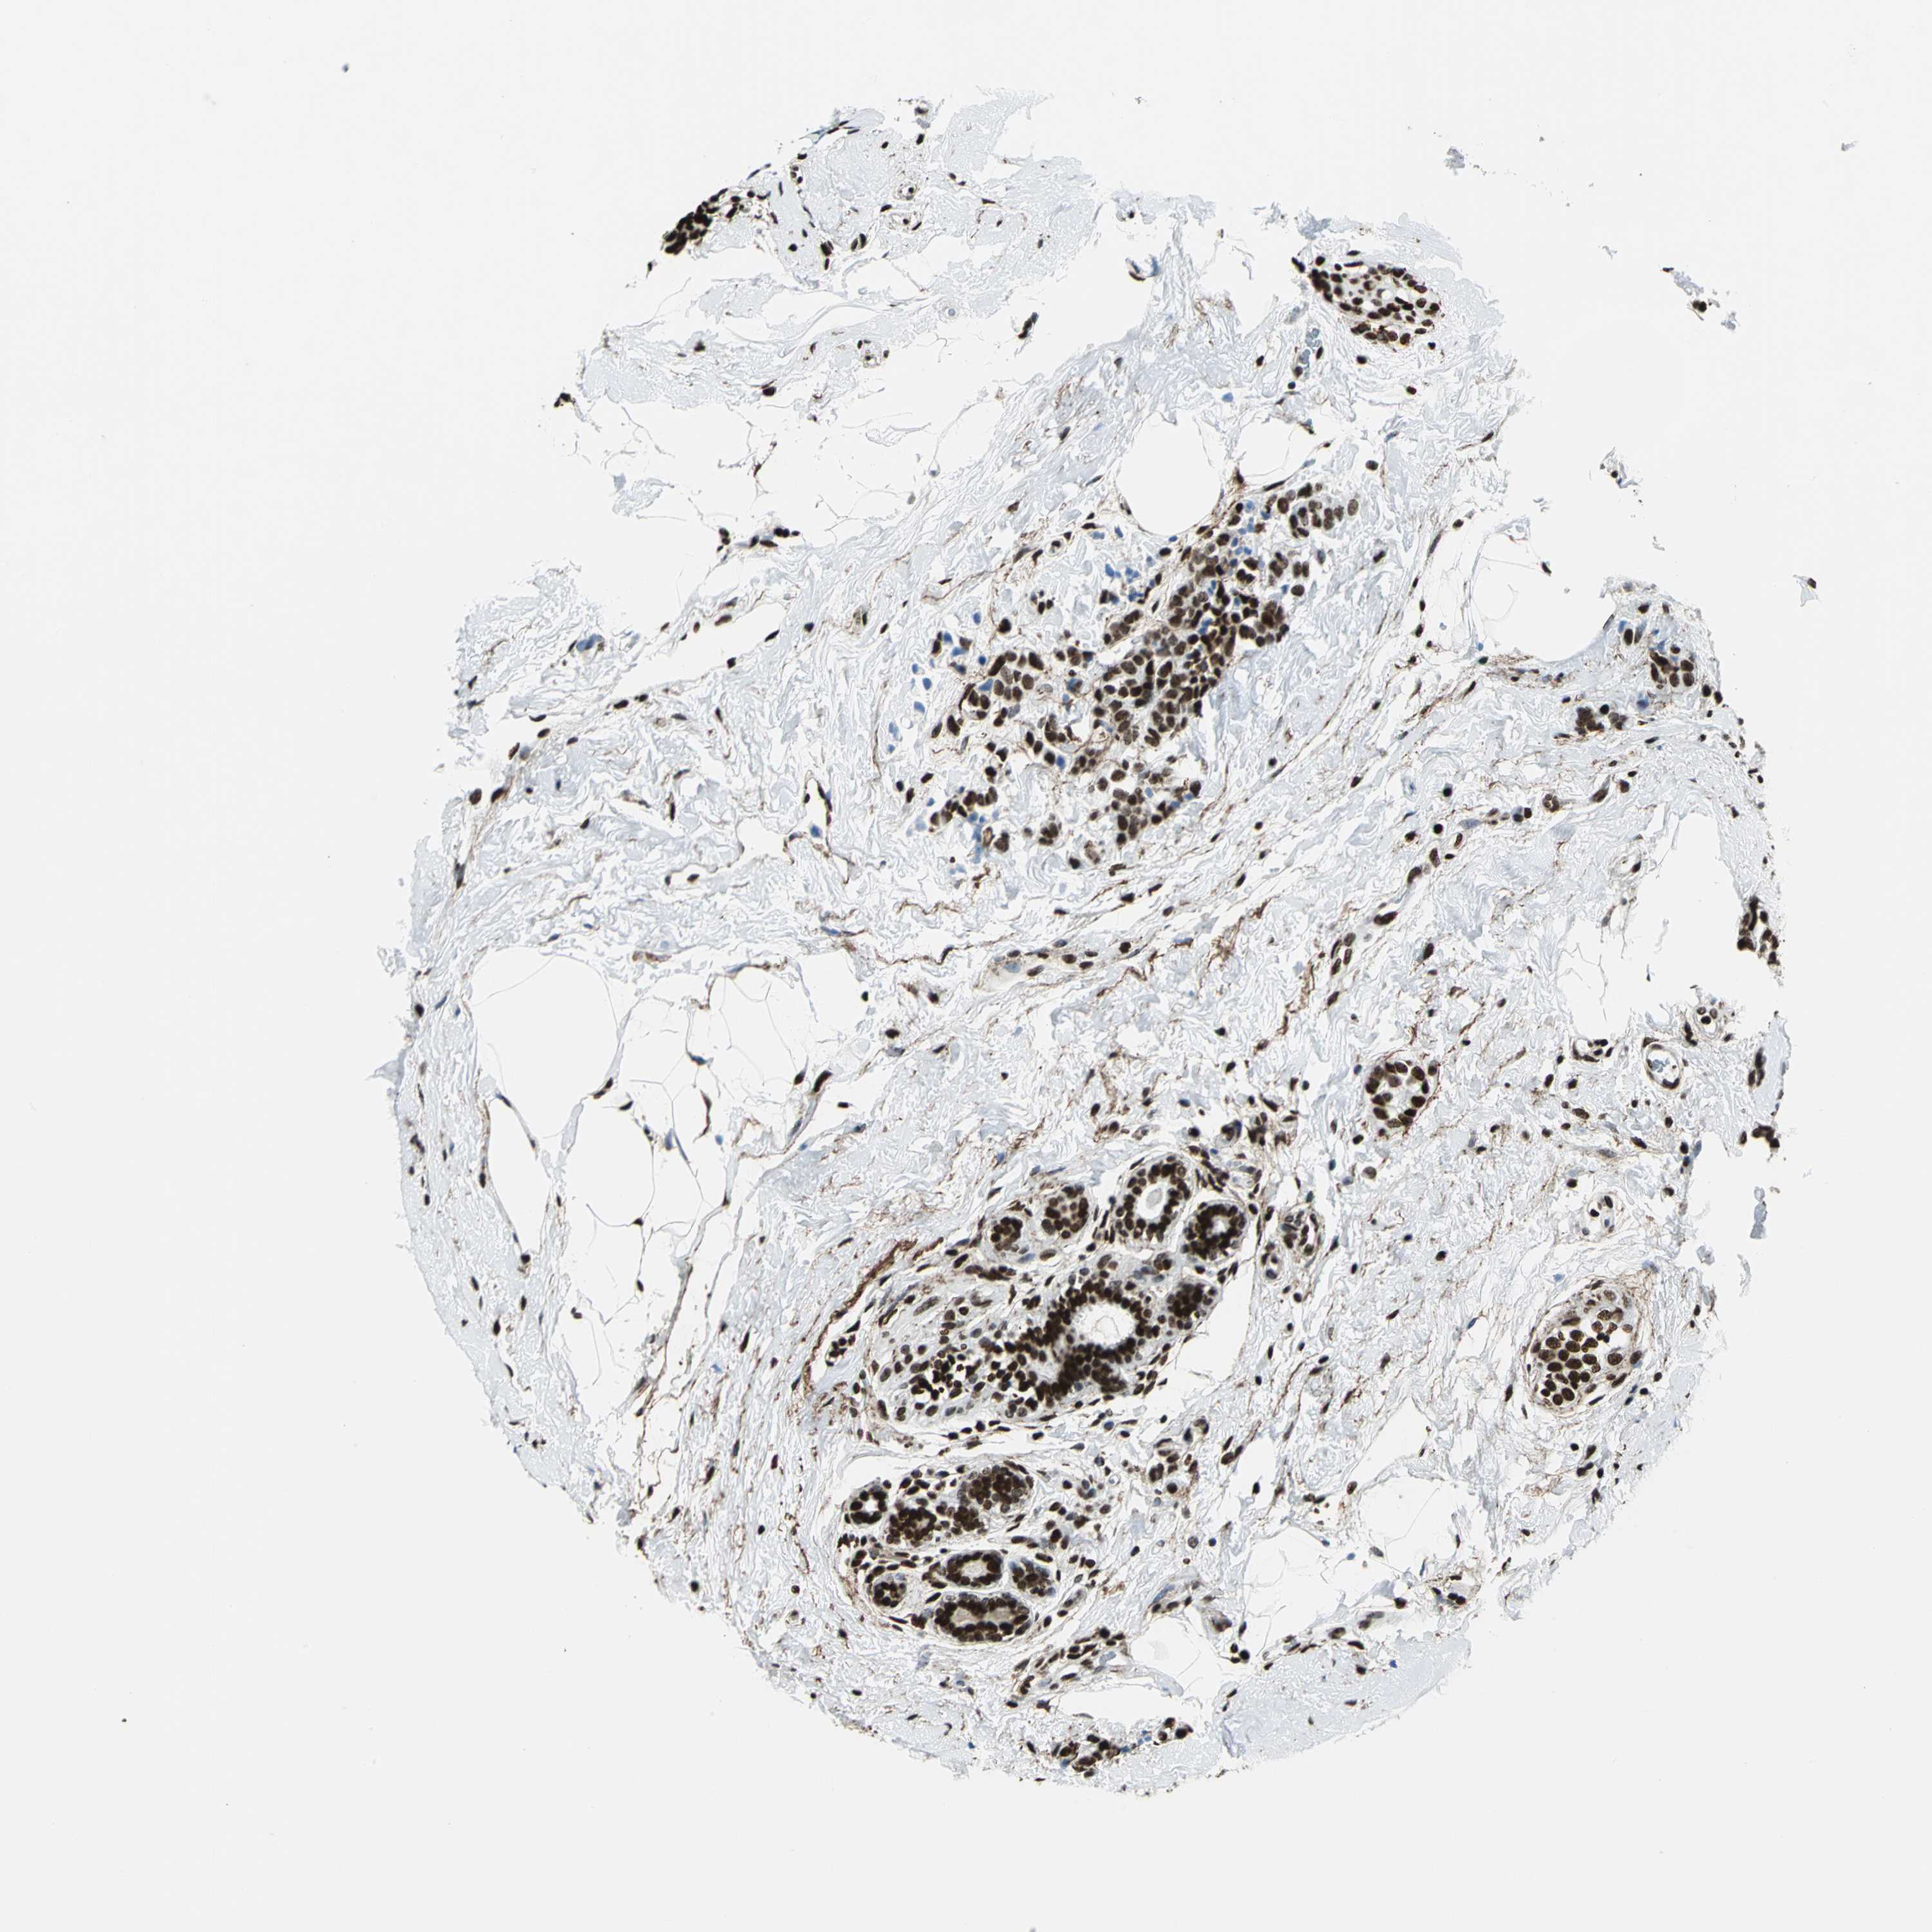

CANCER BREAST CANCER Show tissue menu

BRCA TCGA BRCA VALIDATION PROTEIN EXPRESSION

ANTIBODIES

AND

VALIDATION